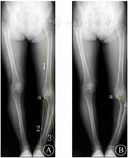

注: A中示线1代表目标力线;线2连接截骨合页点a至踝关节中心,以A点为中心,线2长度为半径,自踝关节中心画一圆与线1相交,连接a点和线1与圆的交点为线3;线2和线3所成夹角即为计划矫正角度.B为根据Miniaci法规划的截骨区域,d为闭合楔形截骨的底边宽度。

本例术中通过两组平行导针确定截骨平面,霍夫曼拉钩保护髌韧带及后方血管神经,摆锯穿透皮质后用薄骨刀进行截骨,术中多次透视,保留内侧皮质的同时逐渐增大截骨量至术前规划水平(图5) ,并保留截去的骨块,以防截骨过多时进行植骨,透视见力线矫正至Fujisawa点,PTS未有明显改变。患者既往有骨髓炎病史,患肢软组织条件差,考虑到使用外固定造成的生活不便,遂选择Tomofix钢板进行内固定,缓慢拧动螺钉闭合截骨端,术后早期负重且未出现合页断裂、截骨端移位等并发症。关闭切口时先松止血带,充分止血并适当松解肌筋膜,以防筋膜间室综合征引起的腓总神经损伤,本例接受了腓骨中段截骨术,随访未出现腓总神经麻痹症状,长期疗效尚需进一步随访。

注: A为剥离胫骨前肌附着点,显露外侧皮质,于截骨位置钻入克氏针以确定截骨方向; B为术中透视监测截骨角度、截骨量及内侧合页的稳定性。